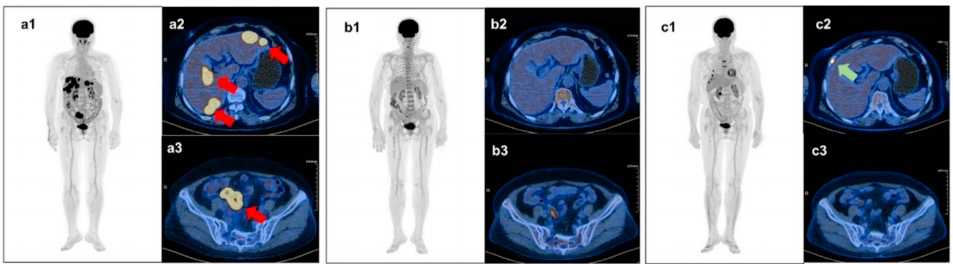

在18例完成6个周期Pola-ZR方案治疗的患者中ORR和CR率均为83%其中包括2例GCB型和13例non-GCB型患者,这表明该方案对不同COO亚型的DLBCL均具有良好的疗效。所有在6个周期后达到CR的患者继续接受泽布替尼单药治疗。研究还提供了1例典型GCB型DLBCL患者的PET/CT结果。该患者在接受3个周期的Pola-ZR方案治疗后达到CR,且随着治疗的继续,病情持续缓解(图2)。

图2. 典型患者的连续评估结果基于PET/CT成像